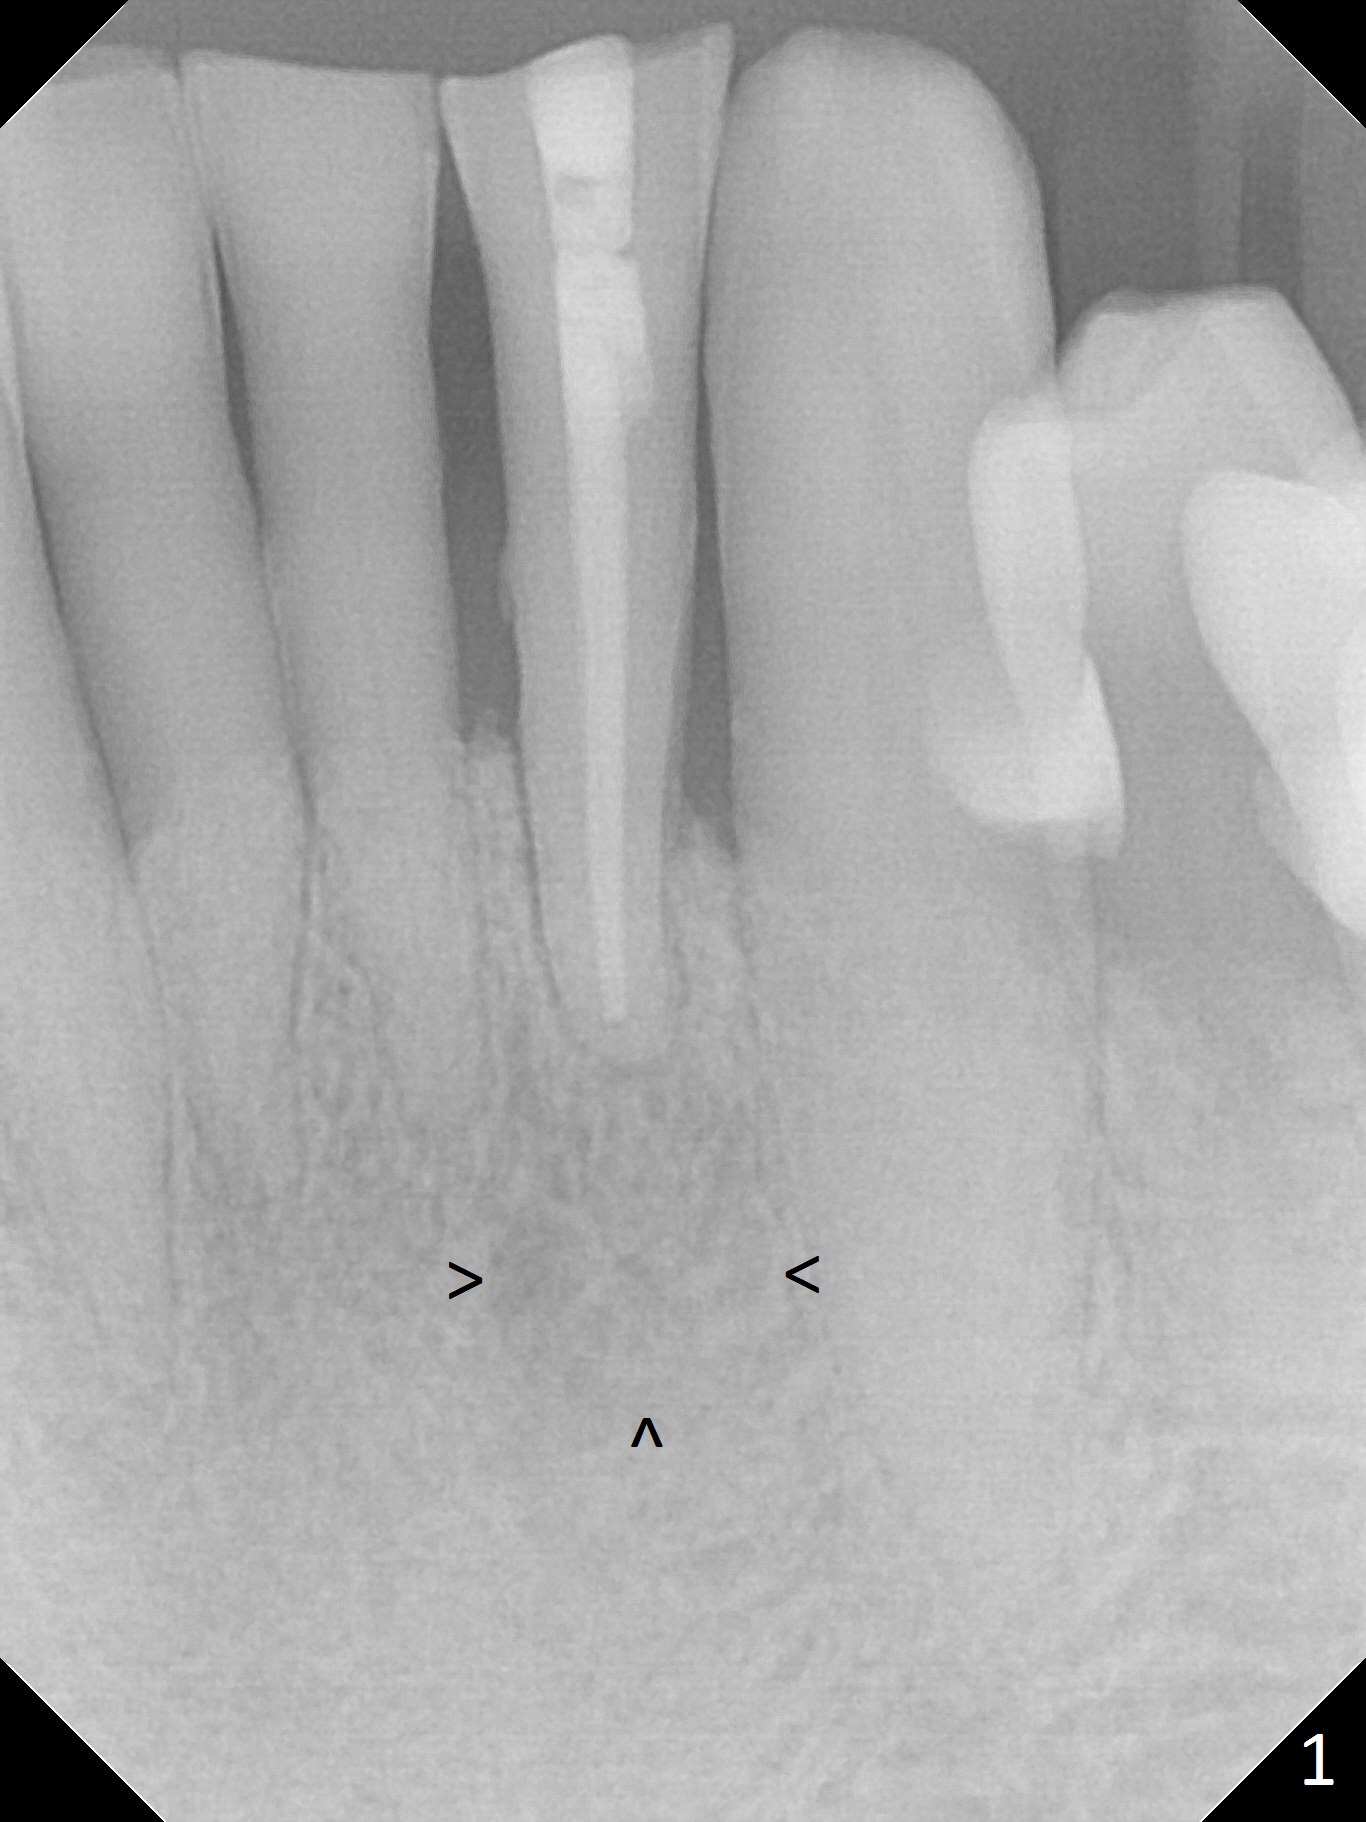

A 71-year-old man requests implant replacement for the lower left lateral incisor, which is discolored and mobile with large periapical radiolucency (Fig.1 arrowheads). The distal crest is lower than the mesial one, which remains the same postop. After extraction (Clindamycin), measure the depth of the gingiva (Fig.2 pink line) to determine the cuff of 1-piece implant (most likely 3x16(4) mm or 2.5x14(4) mm). Load 2% Xylo 1:50,000 Epinephrine for intraligamental injection. Take PA after 1.2 mm drill.